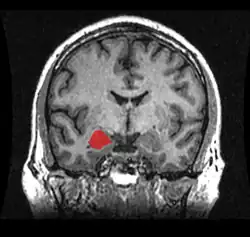

Cuerpo amigdalino

Amígdala cerebral en rojo dentro del encéfalo.

El cuerpo amigdalino, complejo amigdalino o amígdala cerebral es un conjunto de núcleos de neuronas localizadas en la profundidad de los lóbulos temporales de los vertebrados complejos, incluidos los humanos.[1]​ La amígdala forma parte del sistema límbico, y su papel principal es el procesamiento y almacenamiento de reacciones emocionales.[2][3]